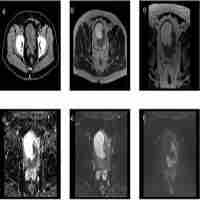

| Abstract | Background: With the large-scale introduction of volumetric modulated arc therapy (VMAT), selection of optimal beam angles for coplanar static-beam IMRT has increasingly become obsolete. Due to unavailability of VMAT in current MR-linacs, the problem has re-gained importance. An application for automated IMRT treatment planning with integrated, patient-specific computer-optimization of beam angles (BAO) was used to systematically investigate computer-aided generation of beam angle class solutions (CS) for replacement of computationally expensive patient-specific BAO. Rectal cancer was used as a model case. Materials and Methods: 23 patients treated at a Unity MR-linac were included. BAOx plans (x=7-12 beams) were generated for all patients. Analyses of BAO12 plans resulted in CSx class solutions. BAOx plans, CSx plans, and plans with equi-angular setups (EQUIx, x=9-56) were mutually compared. Results: For x>7, plan quality for CSx and BAOx was highly similar, while both were superior to EQUIx. E.g. with CS9, bowel/bladder Dmean reduced by 22% [11%, 38%] compared to EQUI9 (p<0.001)). For equal plan quality, the number of EQUI beams had to be doubled compared to BAO and CS. Conclusions: Computer-generated beam angle CS could replace individualized BAO without loss in plan quality, while reducing planning complexity and calculation times, and resulting in a simpler clinical workflow. CS and BAO largely outperformed equi-angular treatment. With the developed CS, time consuming beam angle re-optimization in daily adaptive MR-linac treatment could be avoided. Further systematic research on computerized development of beam angle class solutions for MR-linac treatment planning is warranted. |